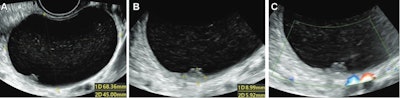

Ultrasound images in 36-year-old woman show a unilocular cyst with a solid component in the right ovary, diagnosed pathologically as a serous cystadenofibroma. (A) Grayscale ultrasound shows the maximal size plane of the mass. (B) Grayscale ultrasound shows the maximal size of the solid component. (C) Color Doppler ultrasound shows the solid component (score 1). This was misdiagnosed by using the Ovarian-Adnexal Reporting and Data System (O-RADS), while both deep-learning models and expert assessment were correct. Images courtesy of the RSNA.The team looked at data from 442 women with an average age of 46.4 years who underwent grayscale and color Doppler ultrasound between January and November 2019. A total of 304 benign and 118 malignant tumors were included. The women were divided into a training and validation data set (337 women) and a test data set (85 women).